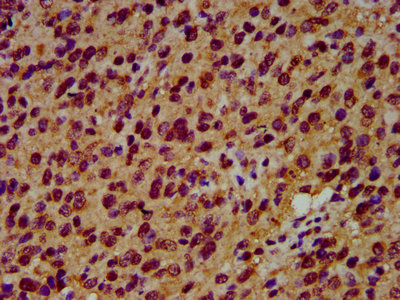

IHC image of CSB-PA021288LA01HU diluted at 1:600 and staining in paraffin-embedded human glioma performed on a Leica BondTM system. After dewaxing and hydration, antigen retrieval was mediated by high pressure in a citrate buffer (pH 6.0). Section was blocked with 10% normal goat serum 30min at RT. Then primary antibody (1% BSA) was incubated at 4°C overnight. The primary is detected by a biotinylated secondary antibody and visualized using an HRP conjugated SP system.

IHC image of CSB-PA021288LA01HU diluted at 1:600 and staining in paraffin-embedded human pancreatic cancer performed on a Leica BondTM system. After dewaxing and hydration, antigen retrieval was mediated by high pressure in a citrate buffer (pH 6.0). Section was blocked with 10% normal goat serum 30min at RT. Then primary antibody (1% BSA) was incubated at 4°C overnight. The primary is detected by a biotinylated secondary antibody and visualized using an HRP conjugated SP system.